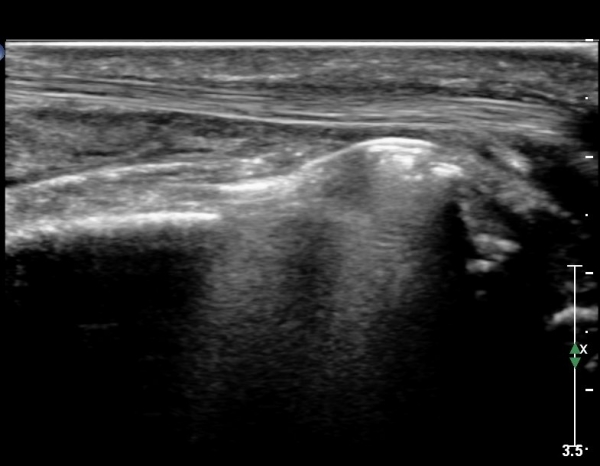

¾Æ·§ÆÈ »óºÎ Ⱦ´Ü¸é°Ë»ç¿¡¼­ Àü°ñ°£ ½Å°æ Áö¹è¸¦ ¹Þ´Â FPL, FDP ¿¡¼­ ½Å°æ¸¶ºñ ¼Ò°ß(°í¿¡ÄÚ ±ÙÀ§Ãà)À»

º¸ÀÌÁö ¾ÊÀ½(»çÁø 1)